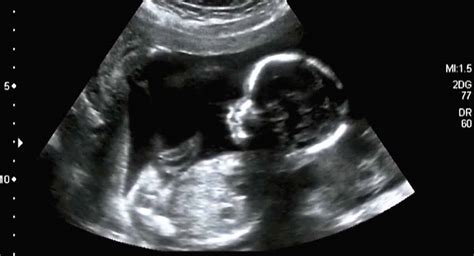

Met een 2D echo ziet u bewegende beelden van uw baby in zwart-wit. Deze echo kan gedurende de gehele zwangerschap worden gemaakt, met de mooiste beelden tot ongeveer de 36e week. Tijdens de echo hoort u het hartje kloppen en ziet u de baby bewegen. Deze 'platte' beelden zijn ideaal voor het plakboek of om snel te delen met familie.